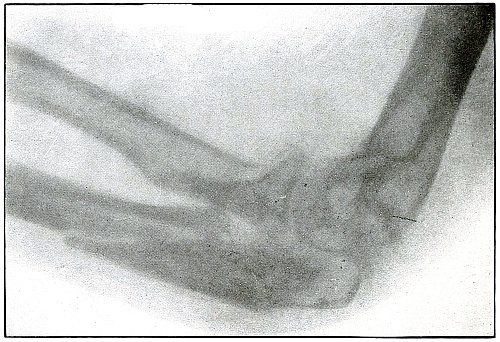

| 17. |

Gunshot fracture, elbow |

44 |

| 18. |

Gunshot fracture, elbow |

46 |

| 19. |

Gunshot fracture, elbow |

48 |

| 20. |

Gunshot fracture, elbow |

50 |